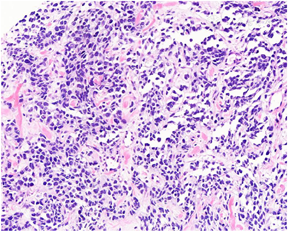

病理检查:送检双侧前列腺穿刺组织8条(左1至左4、右1至右4各一条),长度0.2cm~1.5cm,直径均为0.1cm。镜下观察:其中左2至左4可见良性前列腺腺体,其余5条均为纤维肌性脂肪组织,8条组织内均可见多灶呈小巢、片状以及腺泡样结构的幼稚深染短梭形或卵圆形肿瘤细胞增生、浸润(图2,图3),瘤细胞胞质稀少,核不规则,染色质深,核分裂象和凋亡小体多见,偶见胞质强嗜酸性的横纹肌母细胞样细胞,间质可见带状胶原纤维沉积和局灶的黏液变性(图4,图5)。免疫组织化学染色:肿瘤细胞弥漫核表达MyoD1(图6),大部分表达Myogenin(图7),部分表达结蛋白,弥漫表达CD56,Olig-2局灶表达,约5%(图8),ALK个别细胞表达,弥漫胞质表达WT1和波形蛋白,S-100蛋白阴性,Ki-67增殖指数约70%。荧光原位杂交(FISH)分别检测PAX3和FOXO1基因分离:PAX3和FOXO1基因重排均阳性(图9,图10)。